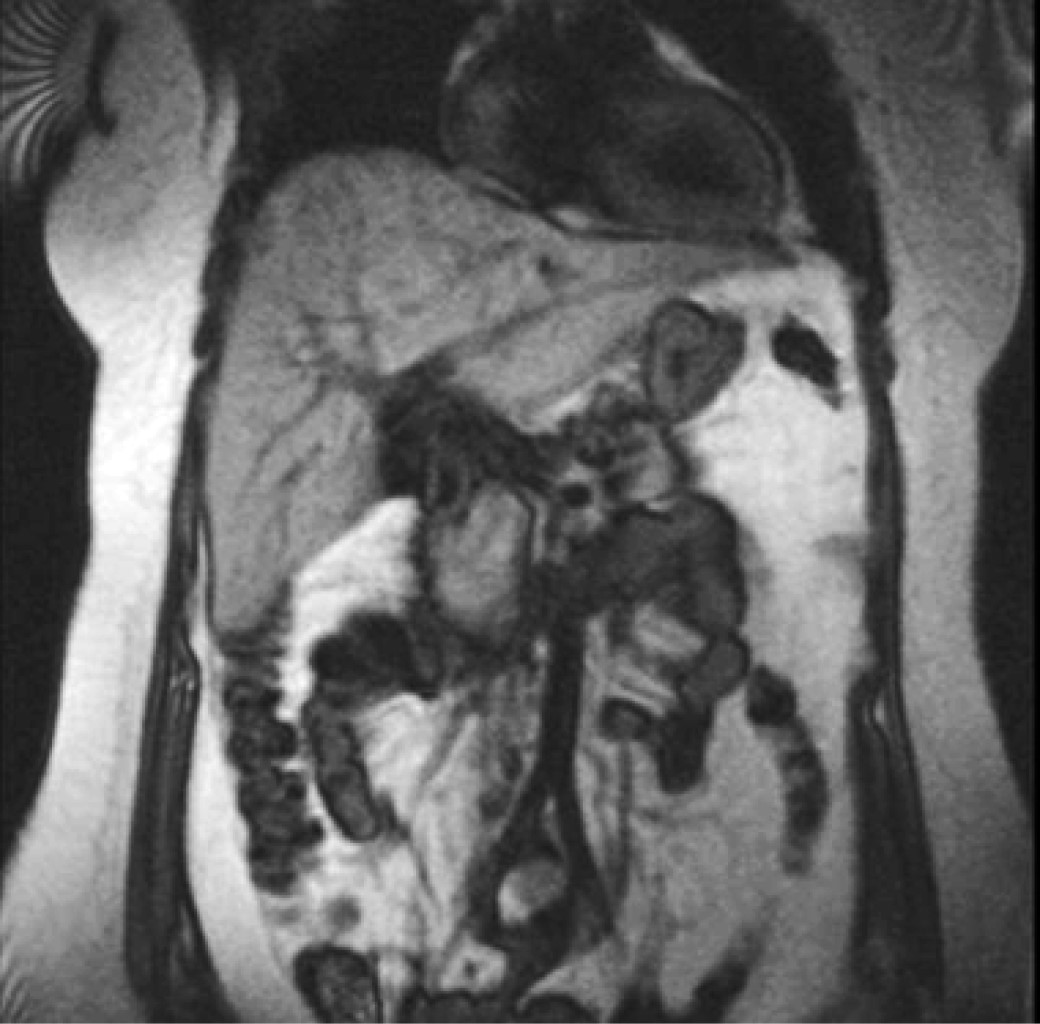

Paciente femenino de 29 años de edad, sin antecedentes de importancia, índice de masa corporal 28.5 kg/m2, inicia padecimiento con dolor súbito a nivel de hipocondrio derecho, irradiado a región escapular, por lo que acude a su hospital Instituto Mexicano del Seguro Social (IMSS) Unidad Médica de Alta Especialidad (UMAE) No. 14, donde mediante tomografía computarizada (TAC) y resonancia magnética (RM) es diagnosticada una lesión ocupante en lóbulo hepático derecho de 9 cm en su diámetro mayor (Figura 1), sin datos clínicos o bioquímicos de cirrosis hepática (bilirrubina total (BT) 1.20 mg/dl, bilirrubina directa (BD) 0.7 mg/dl, proteínas totales 5.4 g/dl, albúmina 3.4 g/dl tiempo de protrombina 14.4 segundos, índice internacional normalizado (INR) 1.08, plaquetas 217 × 103 cel/mm3) y alfafetoproteína sérica 4 ng/ml.

Figura 1